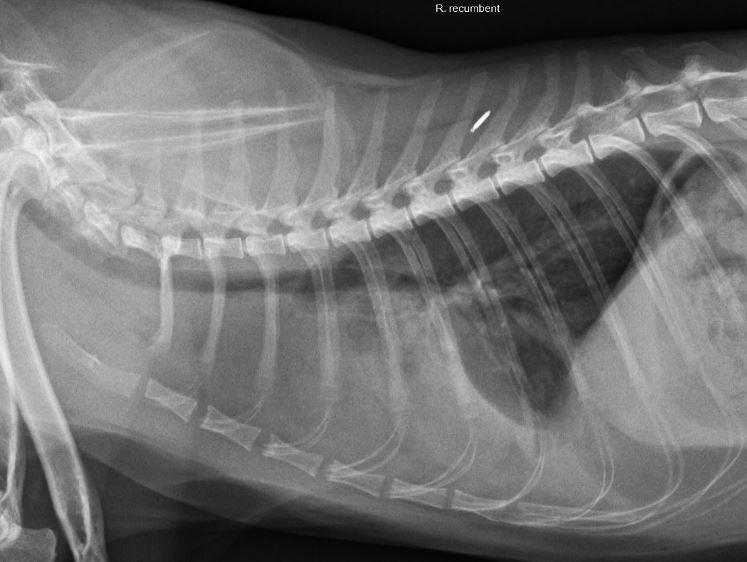

• 貓縱膈型淋巴瘤

縱膈位於胸腔中,為左右肺葉及胸肋膜所包圍的區域,心臟、食道、氣管、胸腺與數個淋巴結等皆分布其中,此區域發生的淋巴瘤即稱為縱膈型淋巴瘤。縱膈型淋巴瘤在貓比狗常見,於約30年前的報告中,甚至佔了所有貓淋巴瘤的60-70%,近年來由於貓白血病的發生率大幅下降,縱膈型淋巴瘤的發生率也大幅減少(目前為所有淋巴瘤的10-20%)。